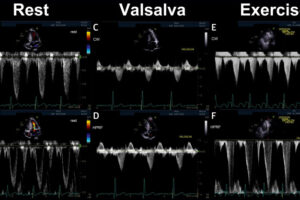

Drs. Mustafa Husaini, Richard Bach, and Sharon Cresci of the Cardiovascular Division published a case report in the August 2024 edition of the Journal of the American Academy of Cardiology, titled “Exercise Testing to Unmask Latent LVOT Obstruction in a Highly Symptomatic Patient With Hypertrophic Cardiomyopathy”.